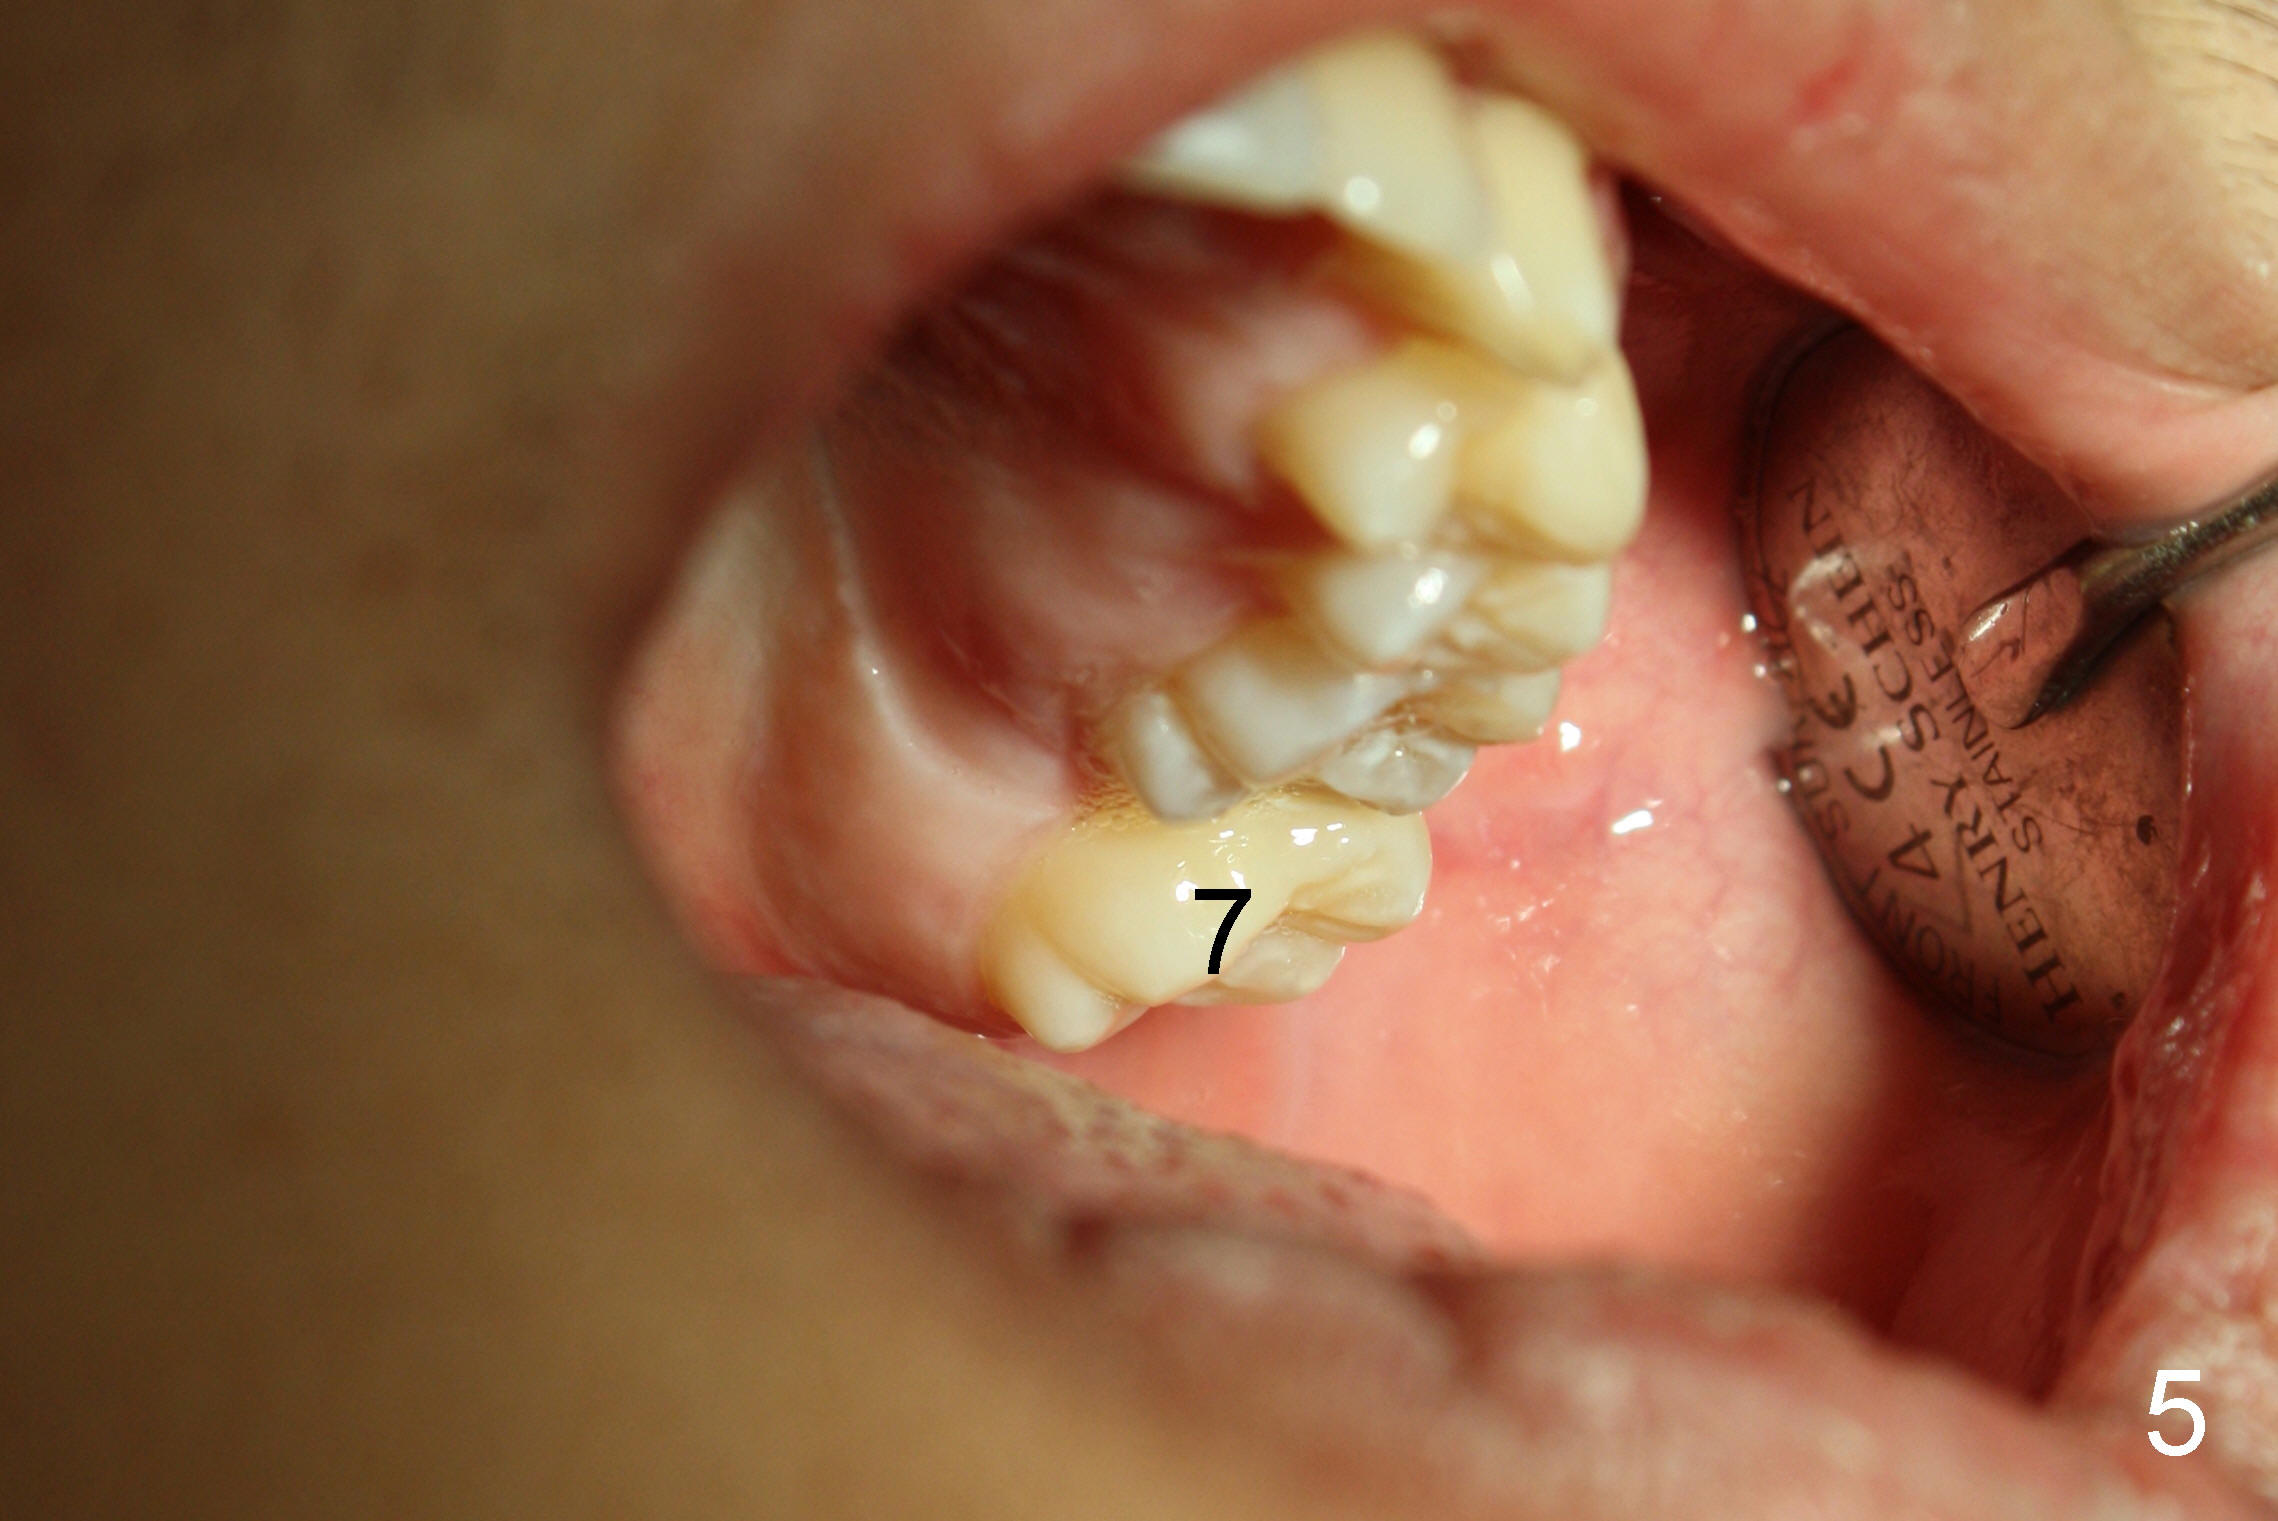

打完下颌神经麻药,乘麻药还没有奏效,拍摄图二至图五,图二,图三显示前牙第一类咬合,而后牙第三类,上颌第二磨牙(7)咬在下颌牙龈(*,仿佛形成白斑(leukoplakia))。图四,图五显示上颌第二磨牙向下伸长。那时我还不具有力挽狂澜能力。那么这四个智齿该拔吗?